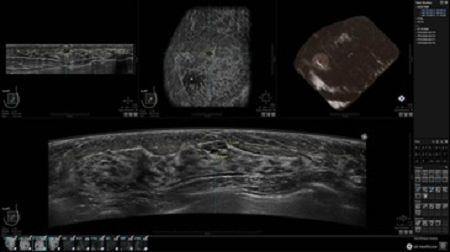

GE INVENIA ABUS – это современный УЗИ аппарат, который создан для точной и эффективной диагностики сканирования с высокой плотностью молочных желез. Выявляемость патологий раковых и предраковых стадий заболевания составляет 55%, что в конечном счете позволяет ставить врачу точные и своевременные диагнозы. Традиционные методы использования маммографии не показывают такой выявляемости, ограничиваясь лишь 3-38%.

УЗИ-аппарат GE INVENIA ABUS позволяет проводить максимально операторонезависимые процедуры, что значительно снижает риск неправильной постановки диагноза и сопутствующие издержки на обработку информации. Система готовит отчет в течение 3-х минут после сканирования, это безусловное преимущество по сравнению с обычным УЗИ сканером.

• Получение объемных 3D изображений с возможностью покадрового просмотра

• Отображение объемных 3D ультразвуковых изображений, которые состоят из традиционных поперечных и воссозданных коронарных и сагиттальных проекций

• Возможность отображения полного 3D изображения

• Многооконный просмотр: 4 - 12 изображений

• Стандартизованная ориентация изображения: «толстый срез» в коронарной плоскости; поперечная; сагиттальная плоскость; радиальный и антирадиальный поворот изображения; просмотр исключительно области интереса